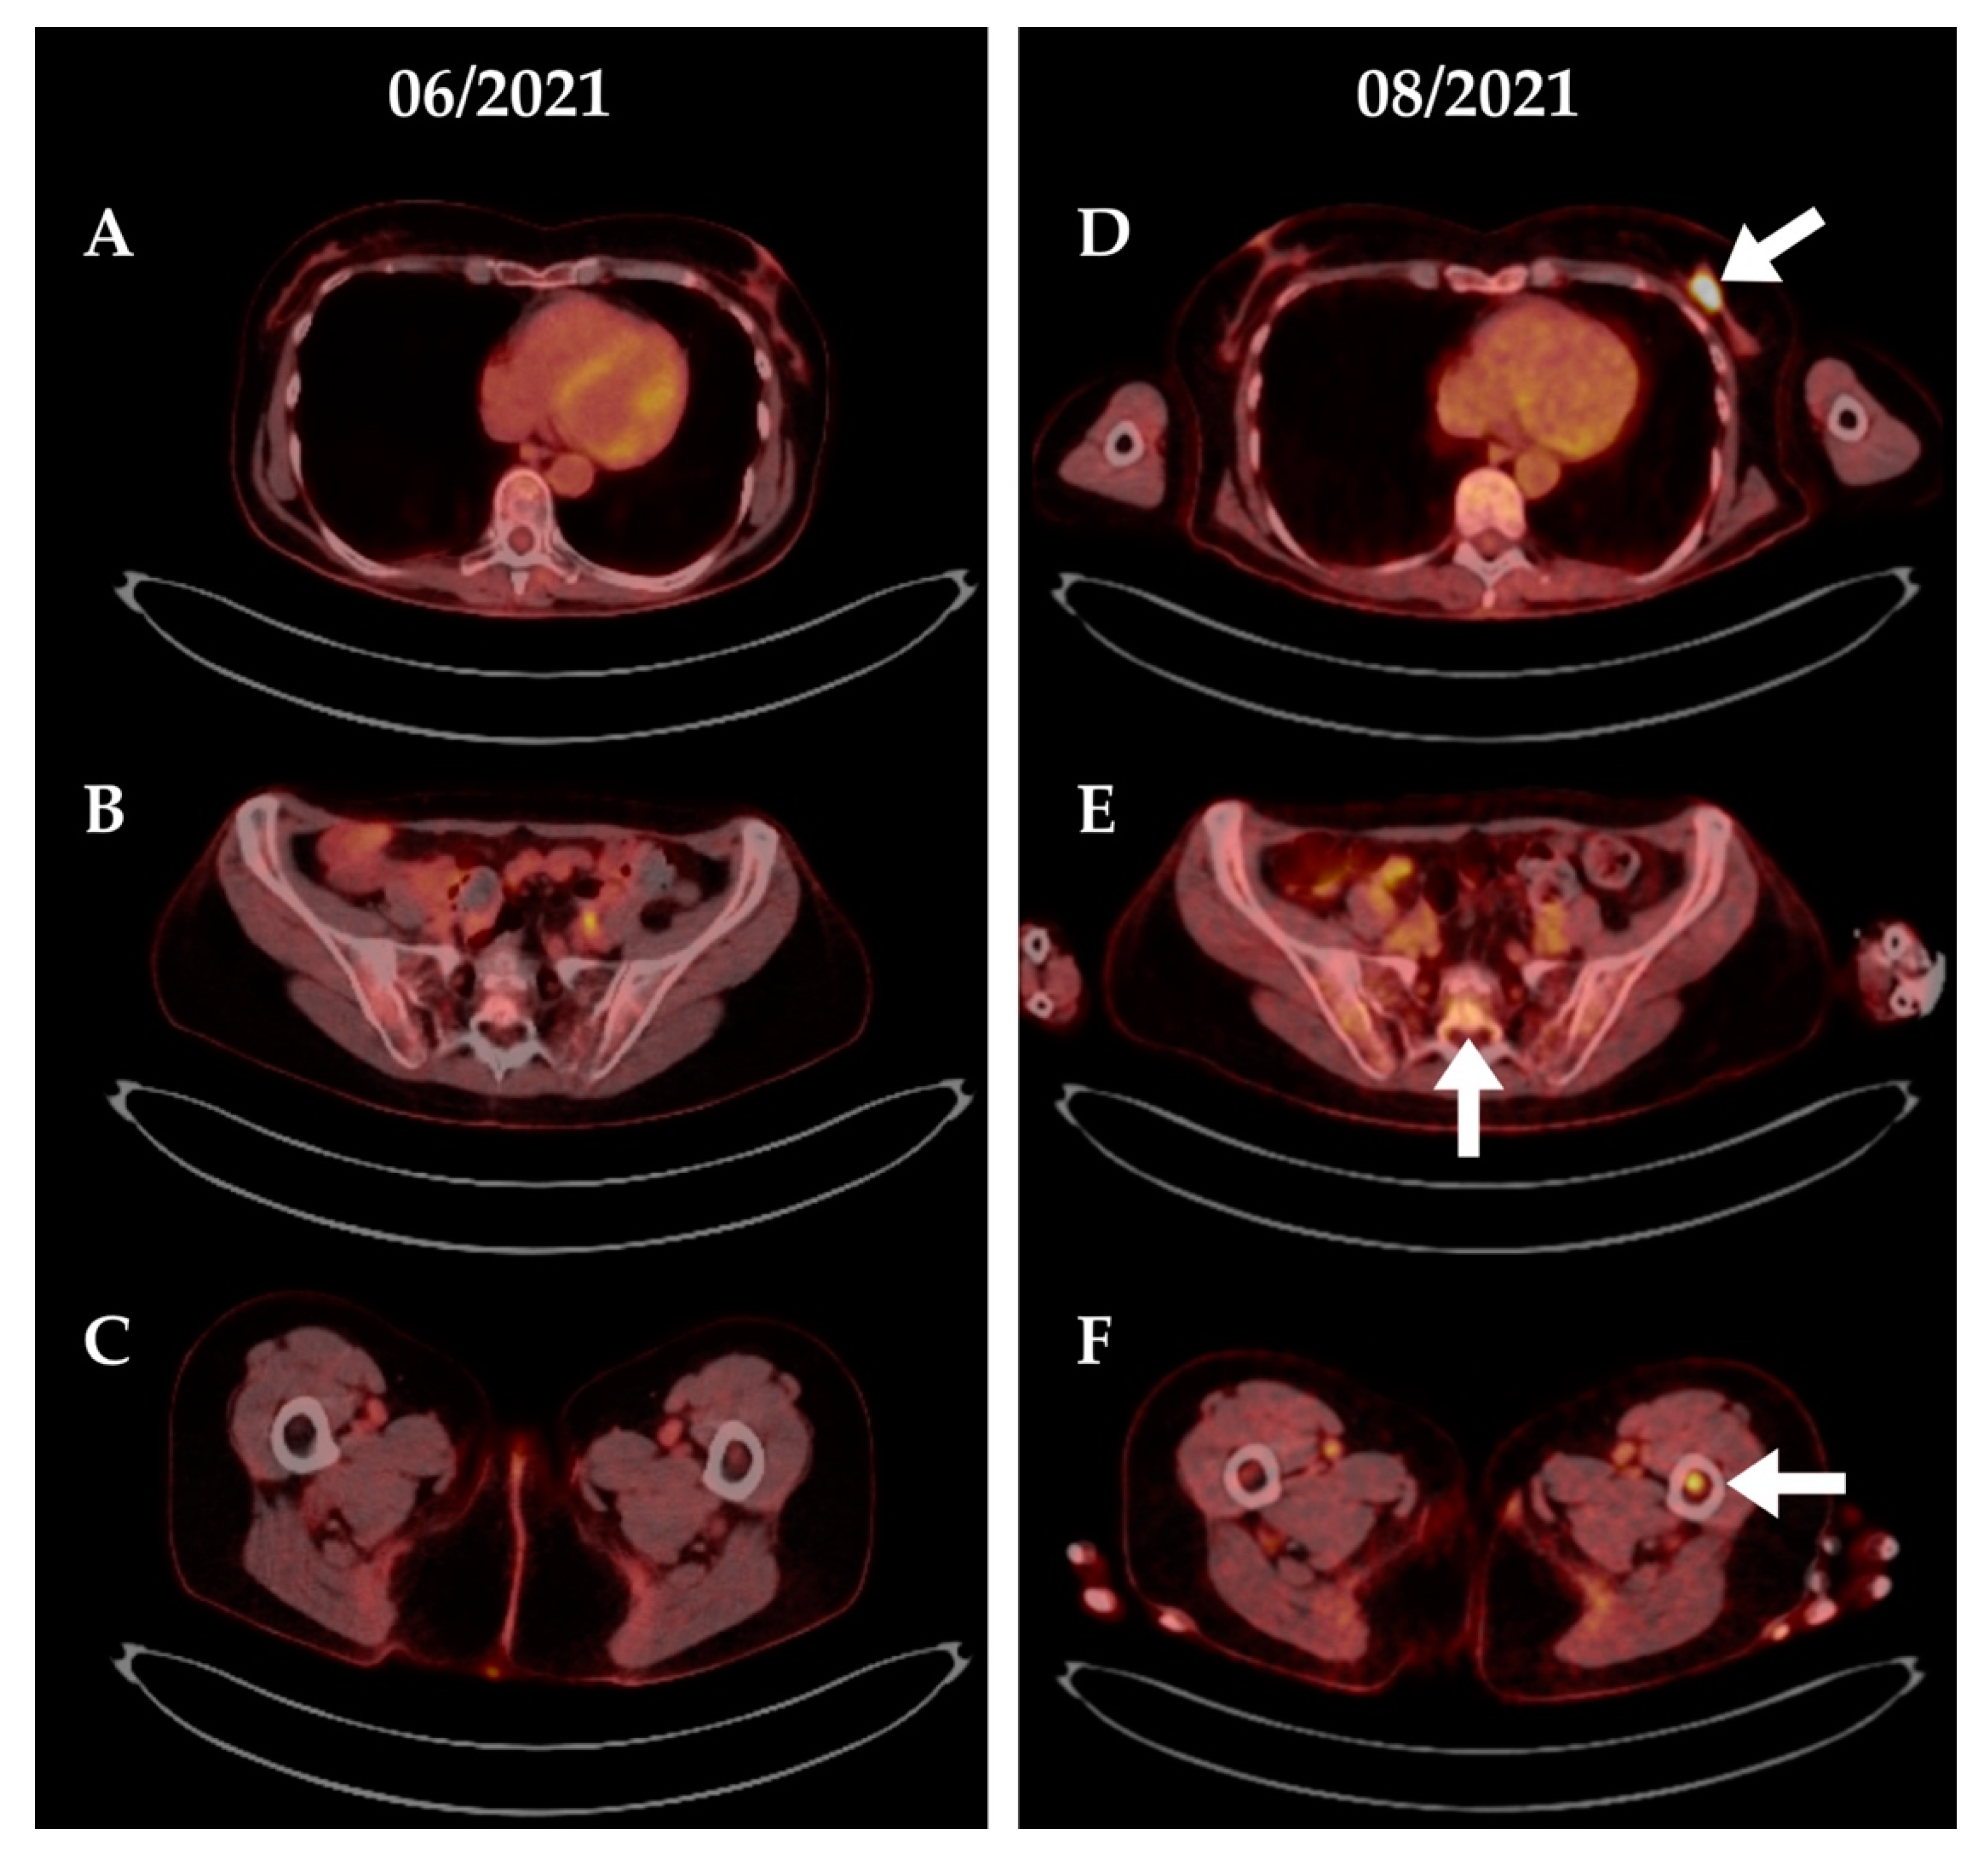

4.1. Patient #1

4.2. Patient #2